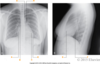

In the standard PA view:

The upper limit of the heart is near the _______ _______ (anteriorly) and the intervertebral disc between ___/___ vertebrae (posteriorly).

In the standard PA view:

The upper limit of the heart is near the sternal angle (anteriorly) and the intervertebral disc between T4/T5 vertebrae (posteriorly).

In the standard PA view:

the Inferior base/Apex of heart is roughly at _____ intercostal space and sits on the diaphragm.

In the standard PA view:

Inferior base/Apex of heart is roughly at 5th intercostal space and sits on the diaphragm.

In the standard PA view:

The right ventricle and the left ventricle (apex) together form the _________ ________ (on the superior surface of the diaphragm)

the right ventricle and the left ventricle (apex) together form the inferior border (on the superior surface of the diaphragm)

In the standard PA view:

the superior vena cava, right atrium and inferior vena cava form the ______ ______ from the R 3rd costal cartilage to the R 6th costal cartilage)

In the standard PA view:

the superior vena cava, right atrium and inferior vena cava form the right border (from the R 3rd costal cartilage to the R 6th costal cartilage)

in the standard PA view:

Aortic arch, pulmonary trunk and left auricle form the ______ ______ (2nd intercostal space to the apex of the heart at the 5th intercostal space – midclavicular line)

In the standard PA view:

Aortic arch, pulmonary trunk and left auricle form the left border (2nd intercostal space to the apex of the heart at the 5th intercostal space – midclavicular line)

The superior border of the heart is at the ____ costal cartilage on the Right of the sternum and the ____ intercostal space on the Left of the sternum.

The superior border of the heart is at the 3rd costal cartilage on the Right of the sternum and the 2nd intercostal space on the Left of the sternum.